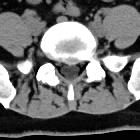

Disc protrusions are a type of disc herniation characterized by protrusion of disc content beyond the normal confines of the intervertebral disc, over a segment less than 25% of the circumference of the disc. The width of the base is wider than the largest diameter of the disc material which projects beyond the normal disc margins. The protrusion must not extend above or below the relevant vertebral endplates .

A disc protrusion is also described in terms of its axial position, into central, subarticular, foraminal, extraforaminal, or anterior locations .